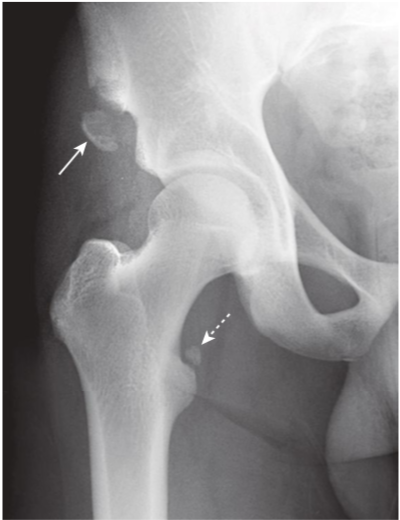

Avulsion fractures, ASIS, and lesser trochanter.

Avulsion fractures are common fractures in which the avulsed fragment is pulled from its parent bone by contraction of a tendon or ligament. They are particularly common in younger individuals who engage in athletic endeavors. There is an avulsion of the anterior superior iliac spine (ASIS) (solid white arrow),which is the site of the insertion of the sartorius muscle. There is also an avulsion of a portion of the lesser trochanter, on which the iliopsoas muscle inserts (dotted white arrow). The patient had participated in track and field events a week prior to these injuries.